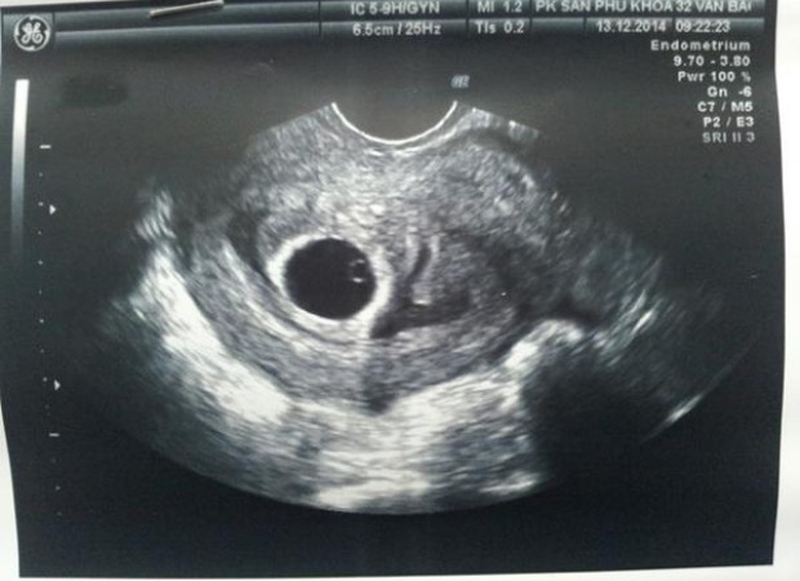

Yolksac hay còn được gọi là túi noãn hoàng, được cấu tạo bởi các nội bì thuộc phôi thai. Đây được coi là một cấu trúc hoàn chỉnh ban đầu của thai nhi. Thông thường, khi bước vào tuần thứ 5 của thai kỳ mẹ bầu sẽ phát hiện được có yolksac thông qua việc siêu âm.

Sự xuất hiện của yolksac còn được coi là sự chuẩn bị cho quá trình hình thành nhau thai ở những giai đoạn sau. Yolksac chứa các protein cần thiết giúp hình thành các tế bào đầu tiên của thai nhi, khi túi ối và phôi thai phát triển thì yolksac cũng tự động phát triển theo sau đó túi noãn hoàng sẽ biến thành cuống noãn hoàng và biến mất để nhường vị trí cho nhau thai.

Thai 7 tuần có yolksac chưa có phôi là thắc mắc đồng thời cũng là nỗi lo lắng của nhiều mẹ bầu. Vậy tình trạng này có gây ra nguy hiểm gì cho bé không?

Thực chất thì việc phát hiện phôi thai hay tim thai thông qua siêu âm không phụ thuộc hoàn toàn vào tình trạng sức khỏe của người mẹ hay sự hình thành, phát triển của thai nhi. Về cơ bản thì đến tuần thứ 7 của thai kỳ, phôi thai sẽ xuất hiện với kích thước khoảng 2mm sau đó theo thời gian nó sẽ to lớn hơn. Nhưng bên cạnh đó, có một số trường hợp khi mang thai đến tuần thứ 7 nhưng chỉ phát hiện có yolksac mà không thấy có phôi thai. Tình trạng này phụ thuộc bởi nhiều nguyên nhân có thể kể đến như: thai nhi phát triển chậm, tính nhầm tuổi thai, trứng bị trống...

Các mẹ bầu cũng cần phải chú ý đến vấn đề siêu âm khi có yolksac, bởi thường thì túi noãn hoàng chỉ dày từ 2 - 5mm, vậy nên nếu kích thước của túi noãn hoàng càng dày thì tỷ lệ hình thành phôi thai sẽ càng thấp. Điều này sẽ gây ra nguy hiểm đối với thai nhi và khả năng sảy thai sẽ cực kỳ cao. Chính vì thế, qua siêu âm mà phát hiện yolksac quá dày thì mẹ bầu cần nhờ đến sự hỗ trợ của bác sĩ để chăm sóc sức khỏe cũng như sử dụng các biện pháp can thiệp phù hợp để giữ lấy sự sống của thai nhi.